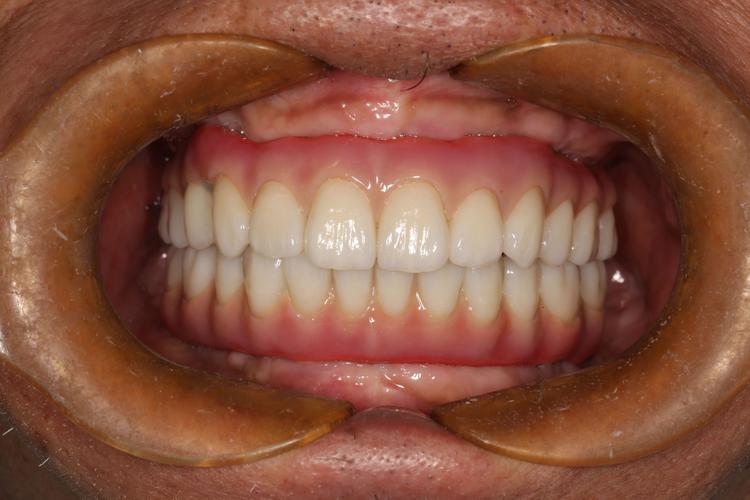

半口All-on-4即刻负重

李先生因牙周炎导致半口牙齿脱落,长期佩戴活动牙,咀嚼困难且易脱落,医生通过CBCT评估,采用All-on-4技术,植入4颗种植体支撑半口牙冠,当天实现临时牙冠负重,即可正常进食,6个月后,永久牙冠安装完成,恢复了90%以上的咀嚼功能,李先生终于能享受美食,生活质量大幅提升。